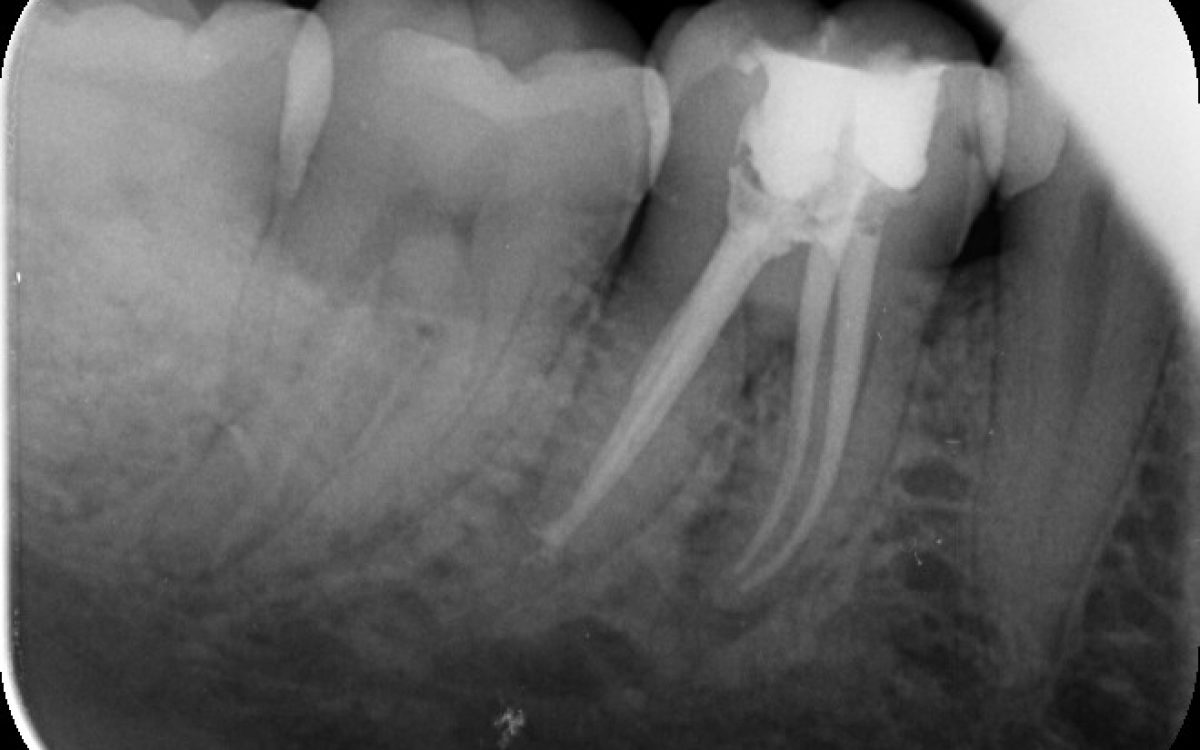

Gyökérkezelés

A gyökérkezelést a fogmegtartó, sőt, fogmegmentő kezelések közé soroljuk, hiszen a kezelés segítségével elkerülhető a fog eltávolítása.

- Nem érzünk fájdalmat, de kontrollvizsgálatkor röntgenen a fog körül elváltozás látszik

Minden esetben több tényezőt vizsgálunk a javaslat megtétele előtt, amennyiben a kiváltó ok megszüntetésére és a fog megtartására is alkalmas a gyökérkezelés, elsőként választandó terápiának ezt javasoljuk.

Hogyan zajlik a gyökérkezelés?

- A fogorvos érzéstelenítés után megnyitja a fogat a rágófelszín felől. A gyökérkezelések gyakran abszolút izolálásban, kofferdam lepedő segítségével történnek.

- Eltávolítja a fogbélkamra tartalmát, felkeresi a gyökércsatornákat, ezeket tágítja, formázza, fertőtlenítő oldatokkal átmossa, majd kiszárítja.

- Első alkalommal gyakran ideiglenes, gyógyszeres töméssel látja el a fogat, mely a gyulladás csökkentésében és a fertőtlenítésben játszik fontos szerepet.Alkalmanként a gyógyszeres tömés cseréjére szükség lehet erősebb gyulladás, fennmaradó panaszok esetén.

- A gyökereket speciális gyökértömő anyaggal látjuk el.

- A fogorvos elkészíti a fog látható részének helyreállítását. Ez történhet töméssel, koronával, vagy betét készítésével.

Egy jól elvégzett gyökérkezelés az erősen fájó, gyulladt fogakat is képes hosszú évekre megtartani, és tünetmentessé tenni.

- Milyen állapotban van eredetileg a fog (pl. szuvas-e, szükséges-e gyökérkezelés, van-e fogágygyulladás)? Ezért első körben egy röntgenfelvételt szoktunk készíteni, hogy a fog szabad szemmel nem látható részeit és környezetét is felmérhessük.